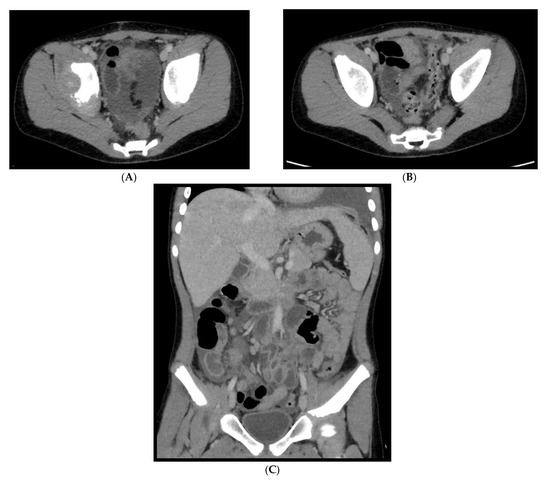

Figure 16. An 11-year-old patient with MIS-C. (AC): Abdominal effusion with cecum and sigma hyper enhancing wall thickening.

In regard to abdominal MIS-C, Caro-Dominguez et al. [38] found that the most common abnormalities in US, CT and MRI were free fluid (71%) and terminal ileum wall thickening (57%) (Figure 16); other less common findings were hepatomegaly, right iliac fossa lymphadenopathy, gallbladder wall oedema, gallbladder sludge, periportal oedema, splenomegaly and haemorrhagic cystitis. According to Palabiyik et al. [40] the most conventional US and CT findings were hepatomegaly and hepatosplenomegaly, followed by periportal and pericholecystic wall oedema, mesenteric lymph nodes in the right lower quadrant, free fluid in the abdomen, temporary invagination, echogenic kidneys and a case of pancreatic alterations. Additionally, in the series of Hameed et al. [43], the most common US and CT abdominal findings were represented by anechoic free fluid (53%), localized inflammatory change within the right iliac fossa (47%), a combination of echogenic expanded mesenteric fat (37%), and multiple mildly enlarged lymph nodes in 47% of cases.